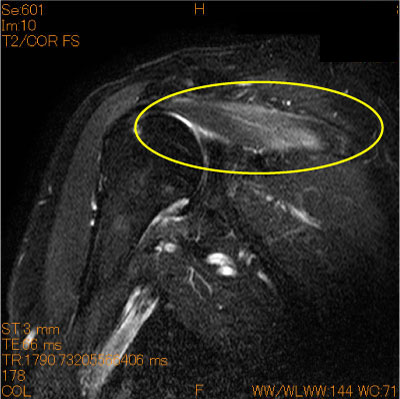

筋腹の脂肪抑制T2 high change-肩関節MRI-

棘上筋の筋腹に脂肪抑制T2 high changeを認めている。DDとして、肉離れ、筋膜炎、neurogenic edemaが考えられる。

症例はヘルペス後の灼熱感のある肩疼痛を半年に渡って訴えている。

RSD(Reflux sympathetic dystrophy)も考慮される。

![]() Obl. Cor T2WI 脂肪抑制 |